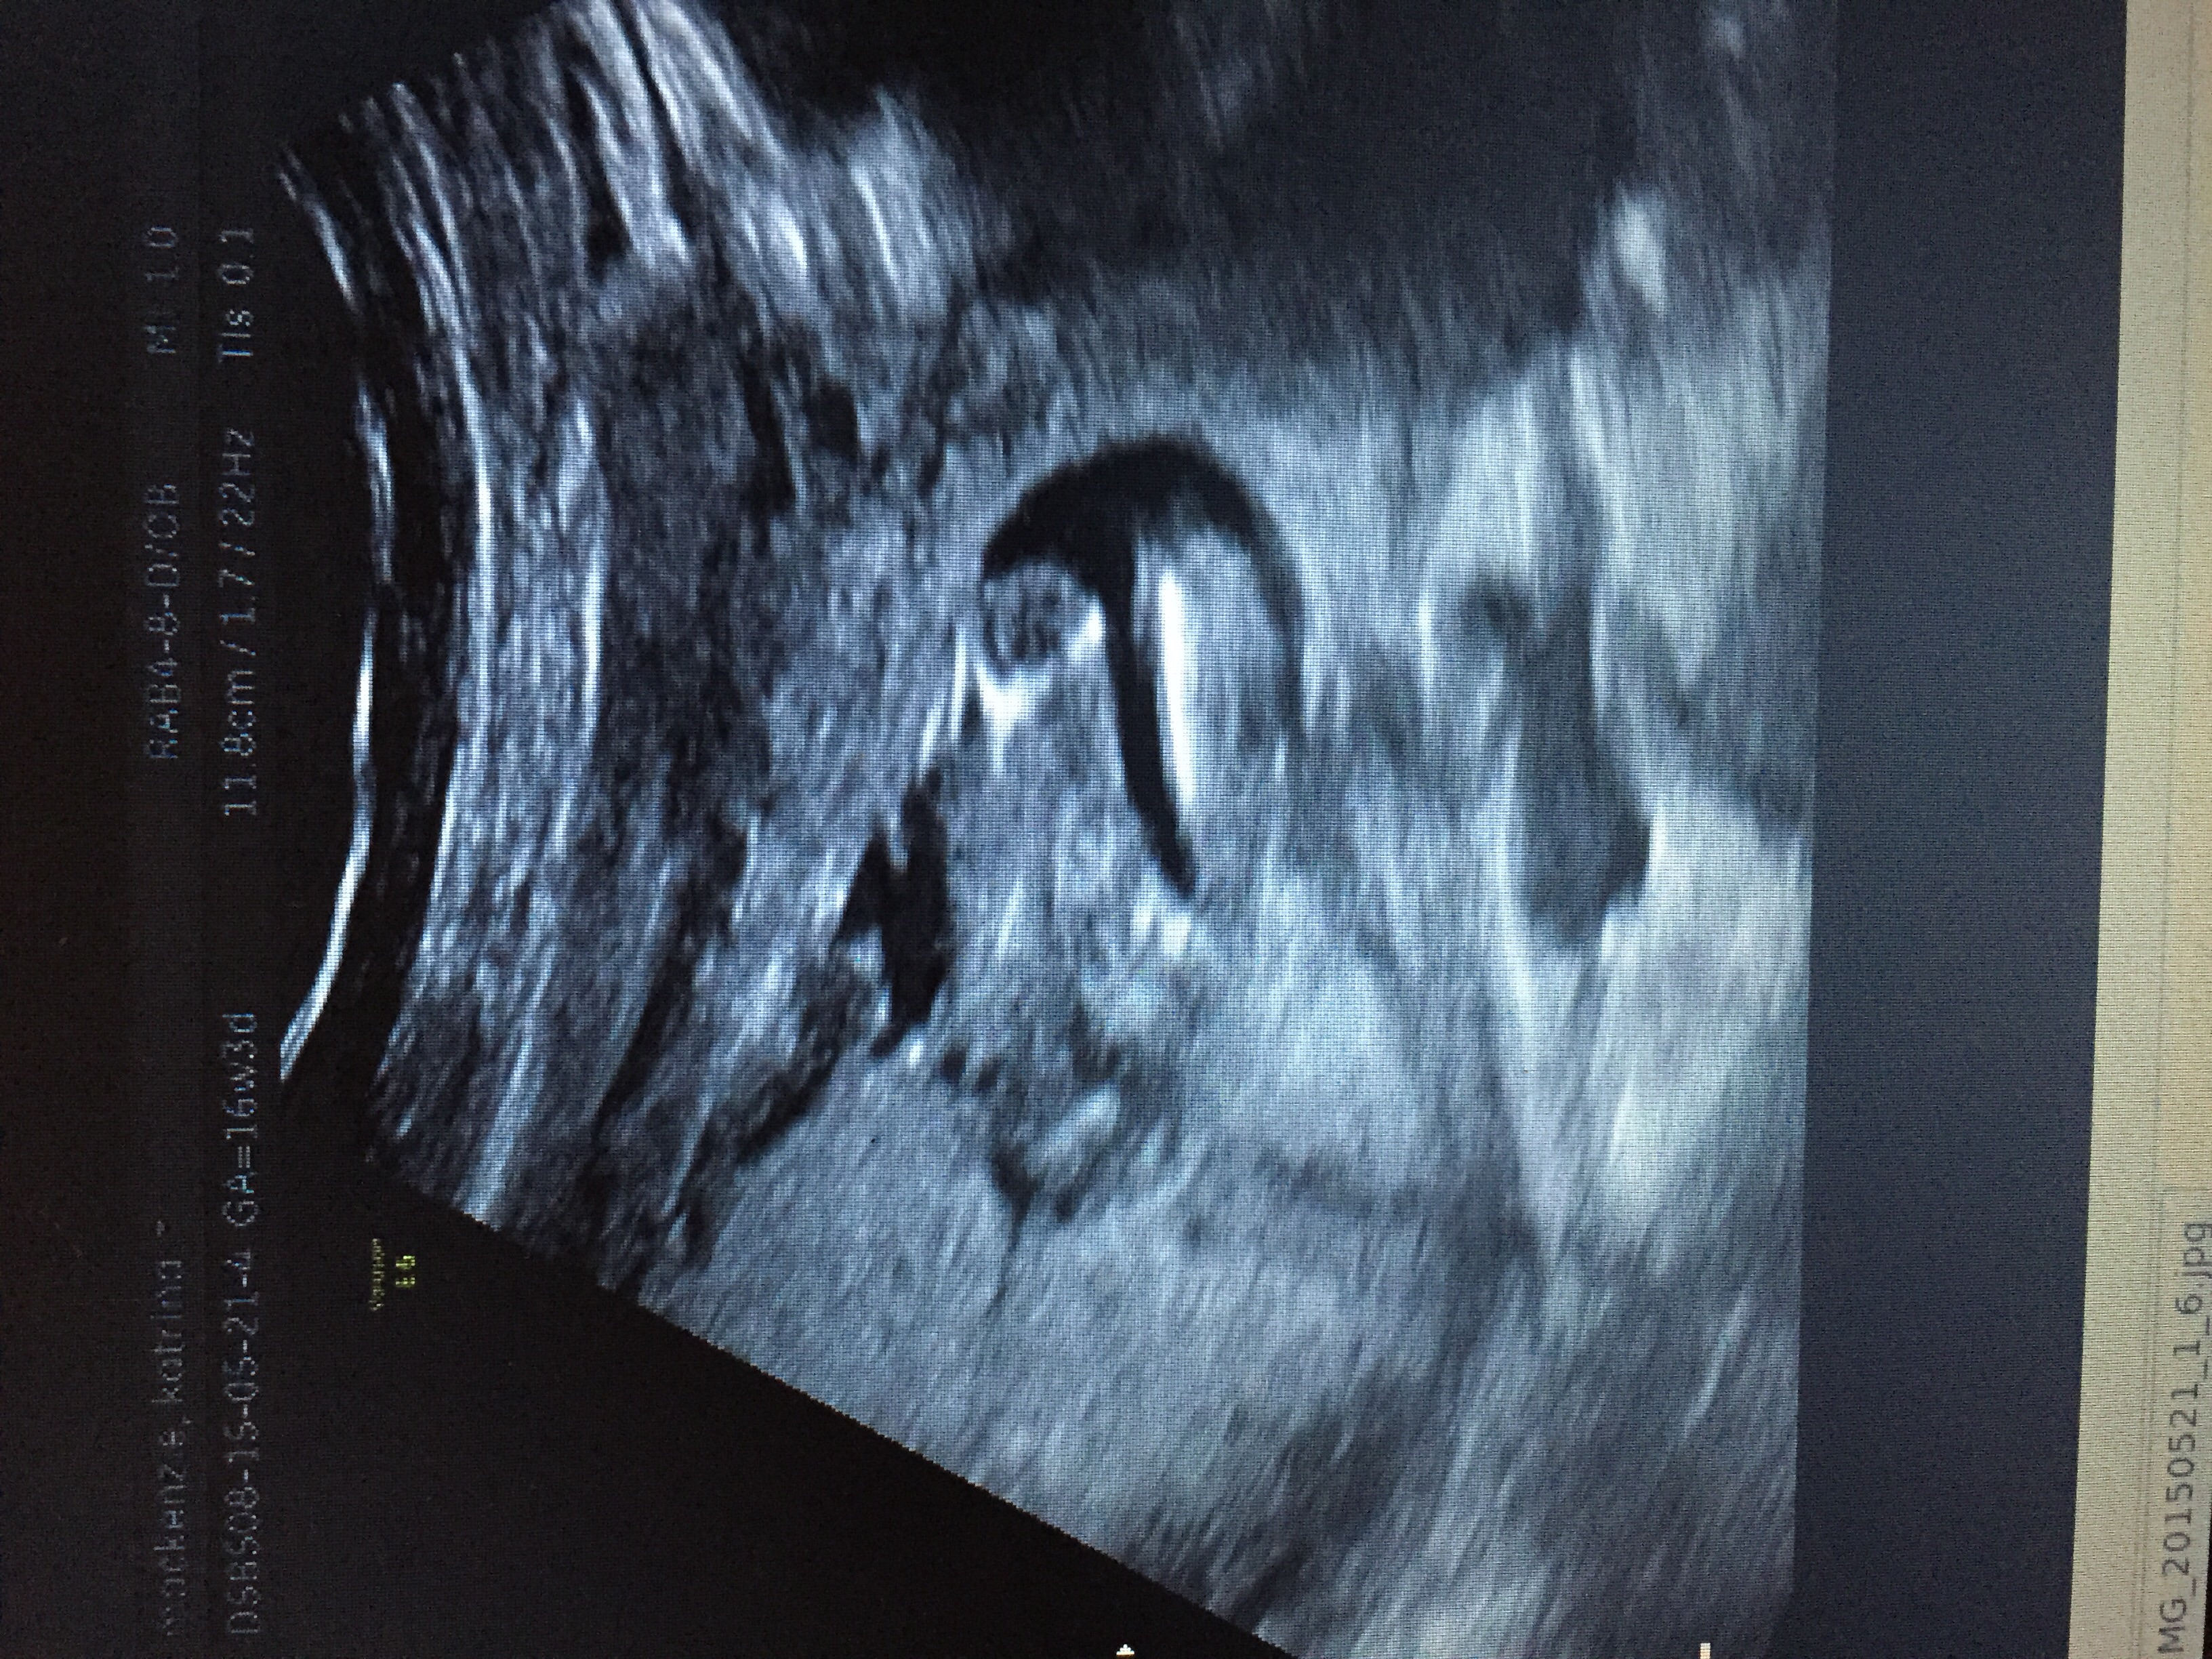

Girl! Looks just like mine actually, I'll attach it x

Attachment 25578

Yes GIRL :)